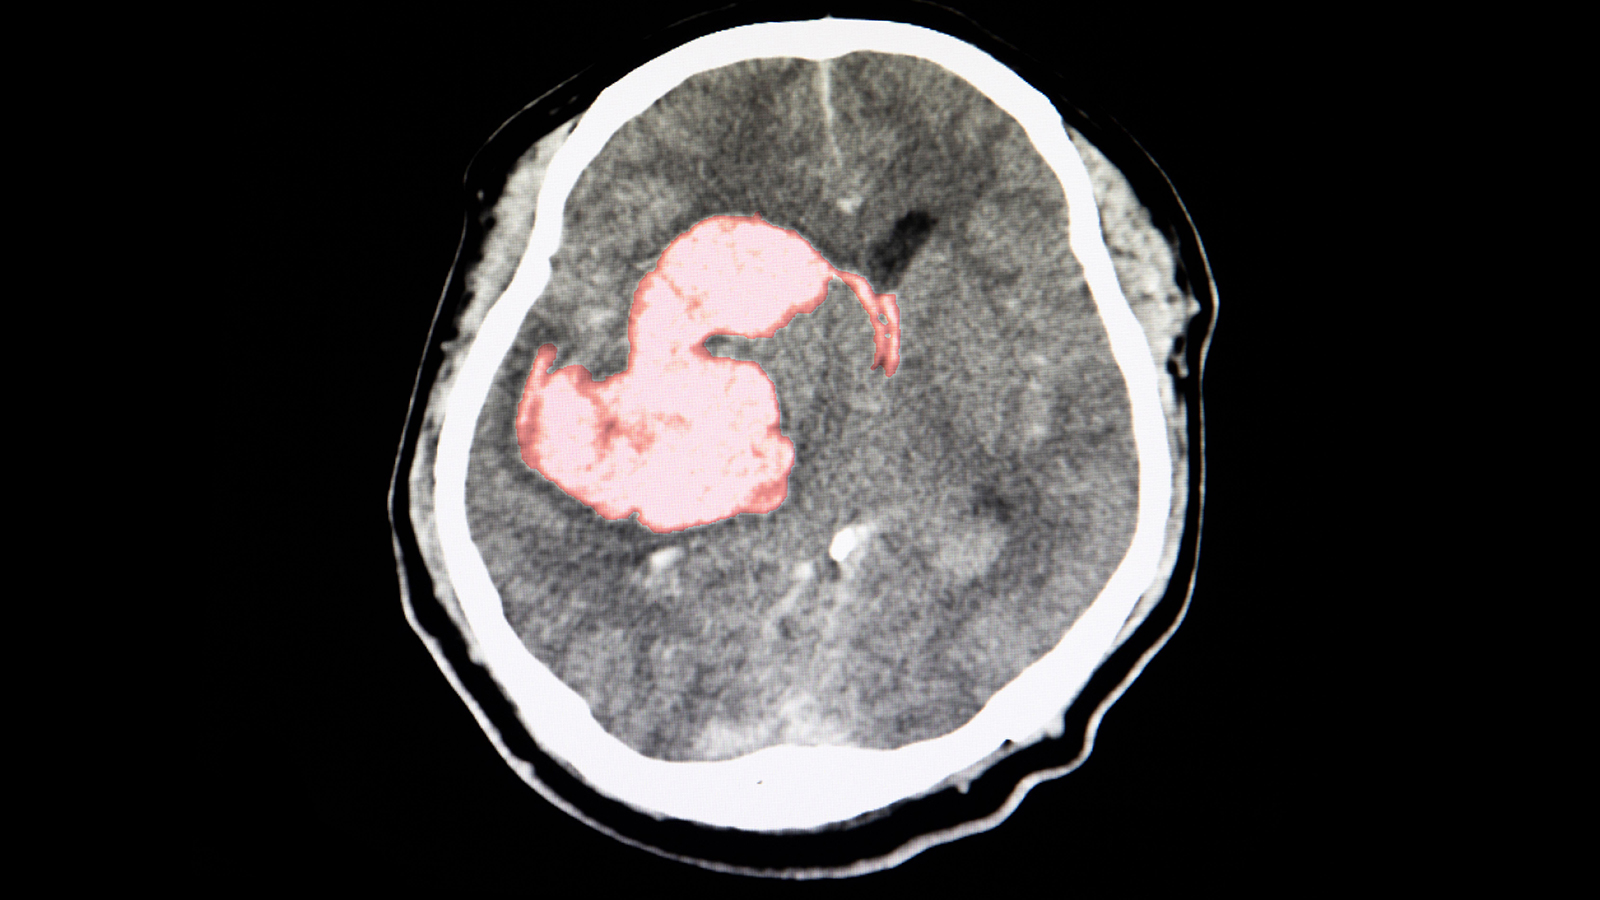

(MedPage Today) — Additional antihypertensive treatment with a three-drug polypill benefitted patients after intracerebral hemorrhage (ICH), the placebo-controlled TRIDENT trial found.